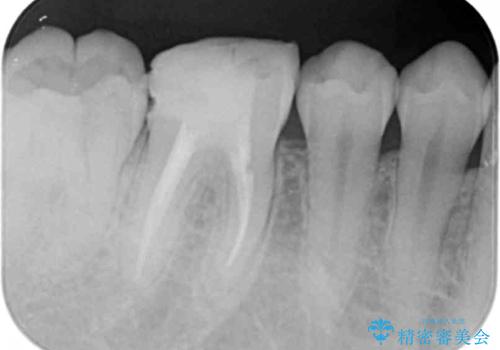

2.

2. 放置してしまった虫歯の治療の治療中